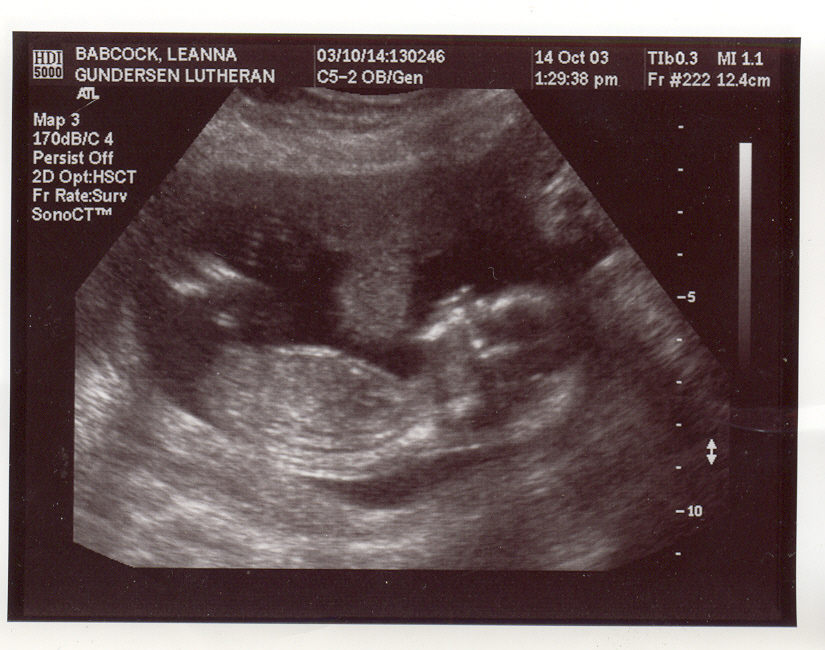

This is my new baby page. I am due at the end of March/start of April, 2004. Here are my first ultrasound pix. They may take a few minutes to load, so be patient. These ultrasound pix were taken Oct. 14th, 2003. We were unable to find out the sex of the baby because it was too early in my pregnancy and also the baby's umbilical cord was between it's legs, and whenever we tried to see what was down there that was blocking our view, and also the baby would put it's hands in the way. I go in for another ultrasound on Nov. 11th. I will post more pix up after then. The baby seems to be healthy at this point and Aidan and I are very excited and preparing for our first child with joy in our hearts! :)